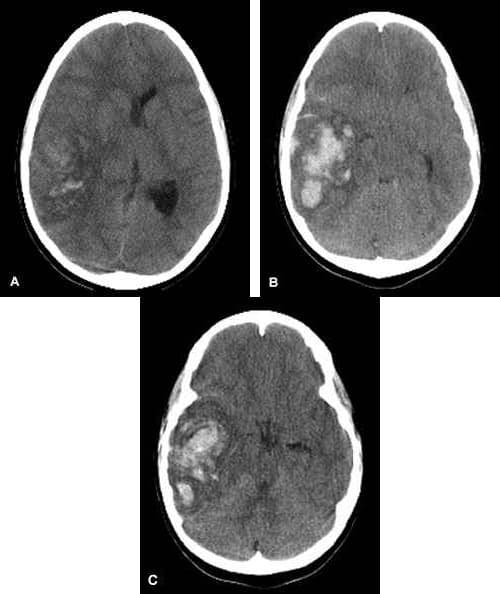

Intraparenchymal hemorrhage (IPH) is one form of intracerebral bleeding in which there is bleeding within brain parenchyma. The other form is intraventricular hemorrhage (IVH). Intraparenchymal hemorrhage accounts for approximately 8-13% of all strokes and results from a wide spectrum of disorders. It is more likely to result in death or major disability than ischemic stroke or subarachnoid hemorrhage, and therefore constitutes an immediate medical emergency. Intracerebral hemorrhages and accompanying edema may disrupt or compress adjacent brain tissue, leading to neurological dysfunction. Substantial displacement of brain parenchyma may cause elevation of intracranial pressure (ICP) and potentially fatal herniation syndromes. Clinical manifestations of intraparenchymal hemorrhage are determined by the size and location of hemorrhage, but may include the following: Hypertension, fever, or cardiac arrhythmias Nuchal rigidity Subhyaloid retinal hemorrhages Altered level of consciousness Anisocoria, nystagmus Focal neurological deficits Putamen - Contralateral hemiparesis, contralateral sensory loss, contralateral conjugate gaze paresis, homonymous hemianopsia, aphasia, neglect, or apraxia Thalamus - Contralateral sensory loss, contralateral hemiparesis, gaze paresis, homonymous hemianopia, miosis, aphasia, or confusion Lobar - Contralateral hemiparesis or sensory loss, contralateral conjugate gaze paresis, homonymous hemianopia, abulia, aphasia, neglect, or apraxia Caudate nucleus - Contralateral hemiparesis, contralateral conjugate gaze paresis, or confusion Brain stem - Tetraparesis, facial weakness, decreased level of consciousness, gaze paresis, ocular bobbing, miosis, or autonomic instability Cerebellum - Ataxia, usually beginning in the trunk, ipsilateral facial weakness, ipsilateral sensory loss, gaze paresis, skew deviation, miosis, or decreased level of consciousness Hypertension Arteriovenous malformation Aneurysm rupture Cerebral amyloid angiopathy Intracranial neoplasm Coagulopathy Hemorrhagic transformation of an ischemic stroke Cerebral venous thrombosis Sympathomimetic drug abuse Moyamoya disease Sickle cell disease Eclampsia or postpartum vasculopathy Infection Vasculitis Neonatal intraventricular hemorrhage Trauma In younger patients, vascular malformations, specifically AVMs and cavernous angiomas are more common causes for hemorrhage.